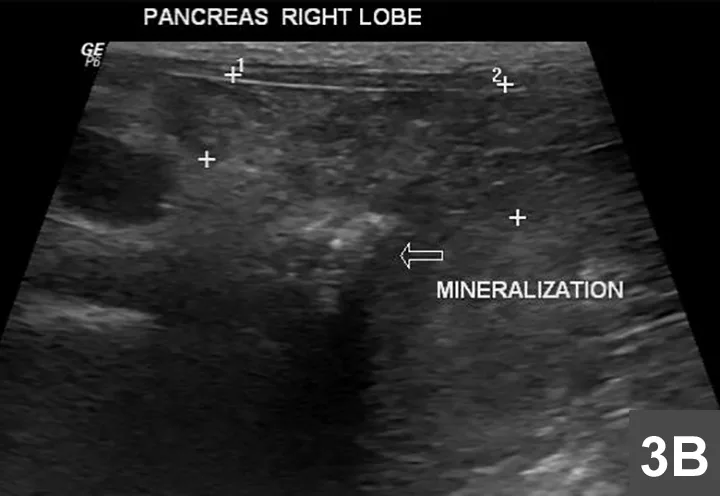

Featured Image

Figure 3B

The + markers indicate a mildly heterogeneous pancreas, while the arrow indicates the region of mineralization associated with beam attenuation.

An area of beam attenuation compatible with mineralization also is visible in the region of the right pancreatic lobe, near the duodenal papilla (Figure 3B). The pancreas appears to be mildly heterogeneous and enlarged at this level, but the peripheral portion of the right pancreatic lobe is normal (homogeneous and much smaller).